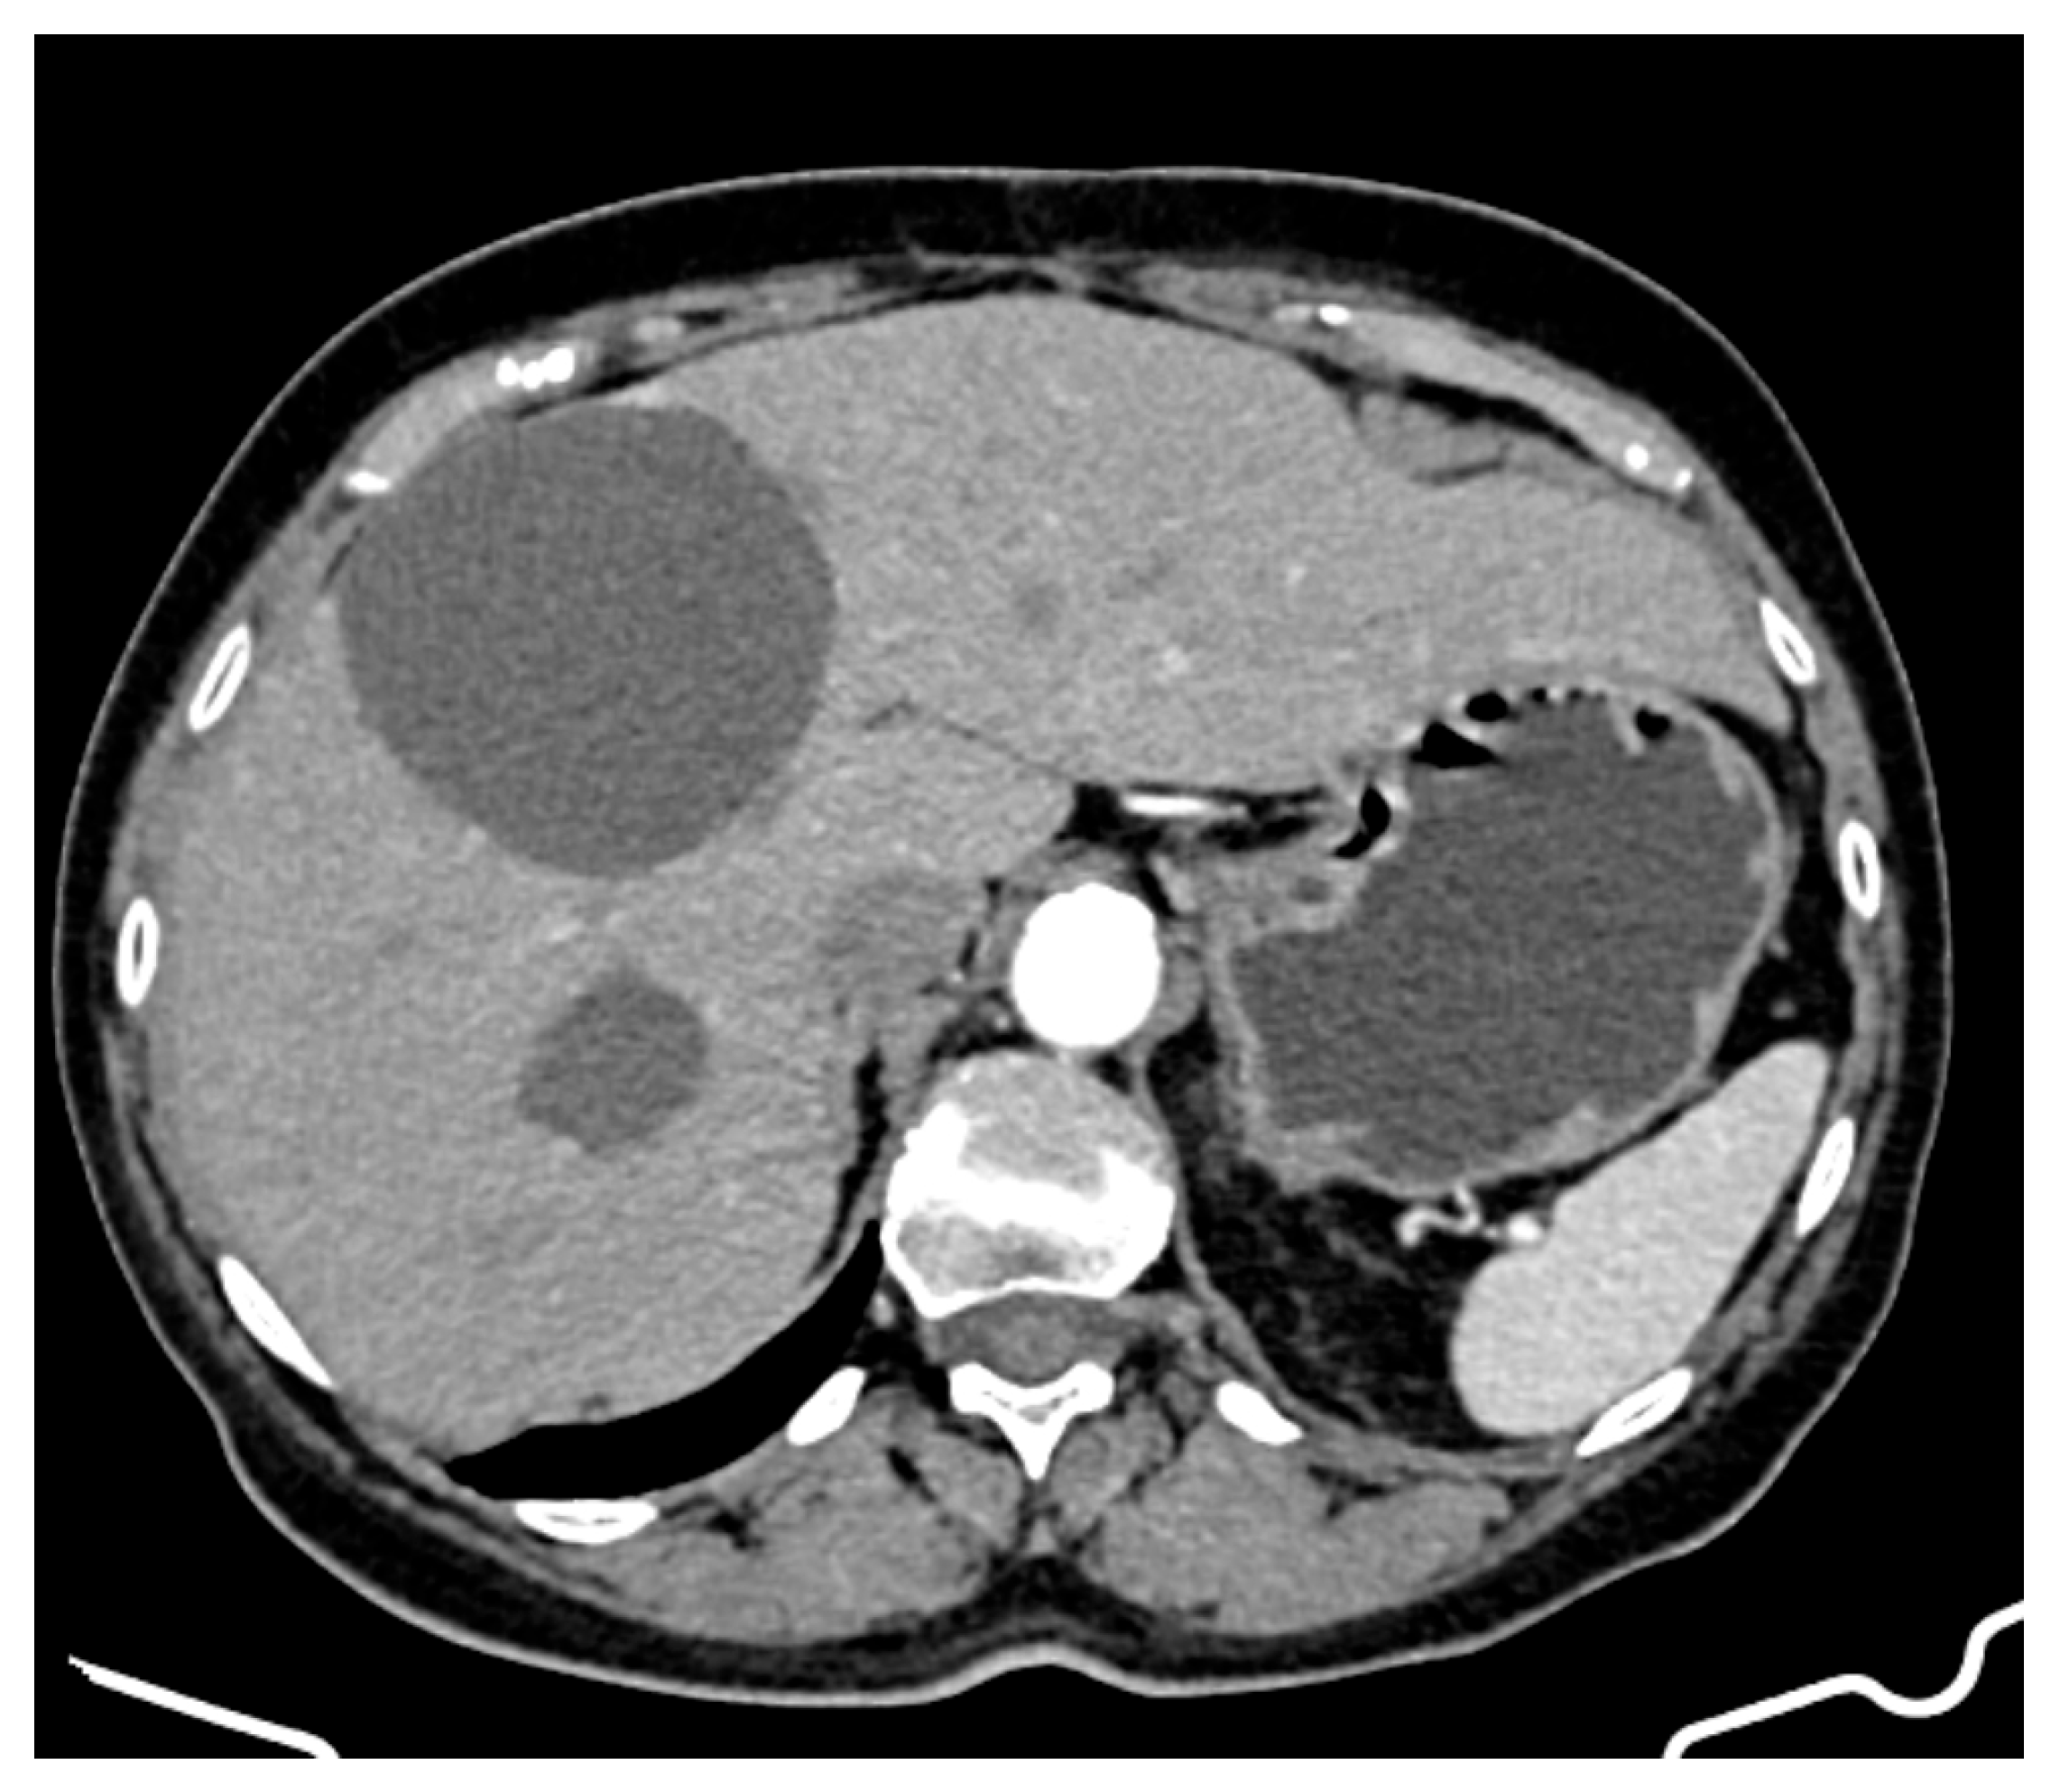

- Hepatic tumour stability: Multiple large cystic hepatic lesions remained stable in size throughout the monitoring period, with no significant new secondary lesions developing. The largest hepatic cystic tumours persisted in segments IV, VI, and VIII, with maximum dimensions of ~8 cm, without major structural changes.

- New large cystic tumour formation;

- Previously known lesions remaining stable;

- An absence of metastatic progression.

2.7. Second Surgical Intervention